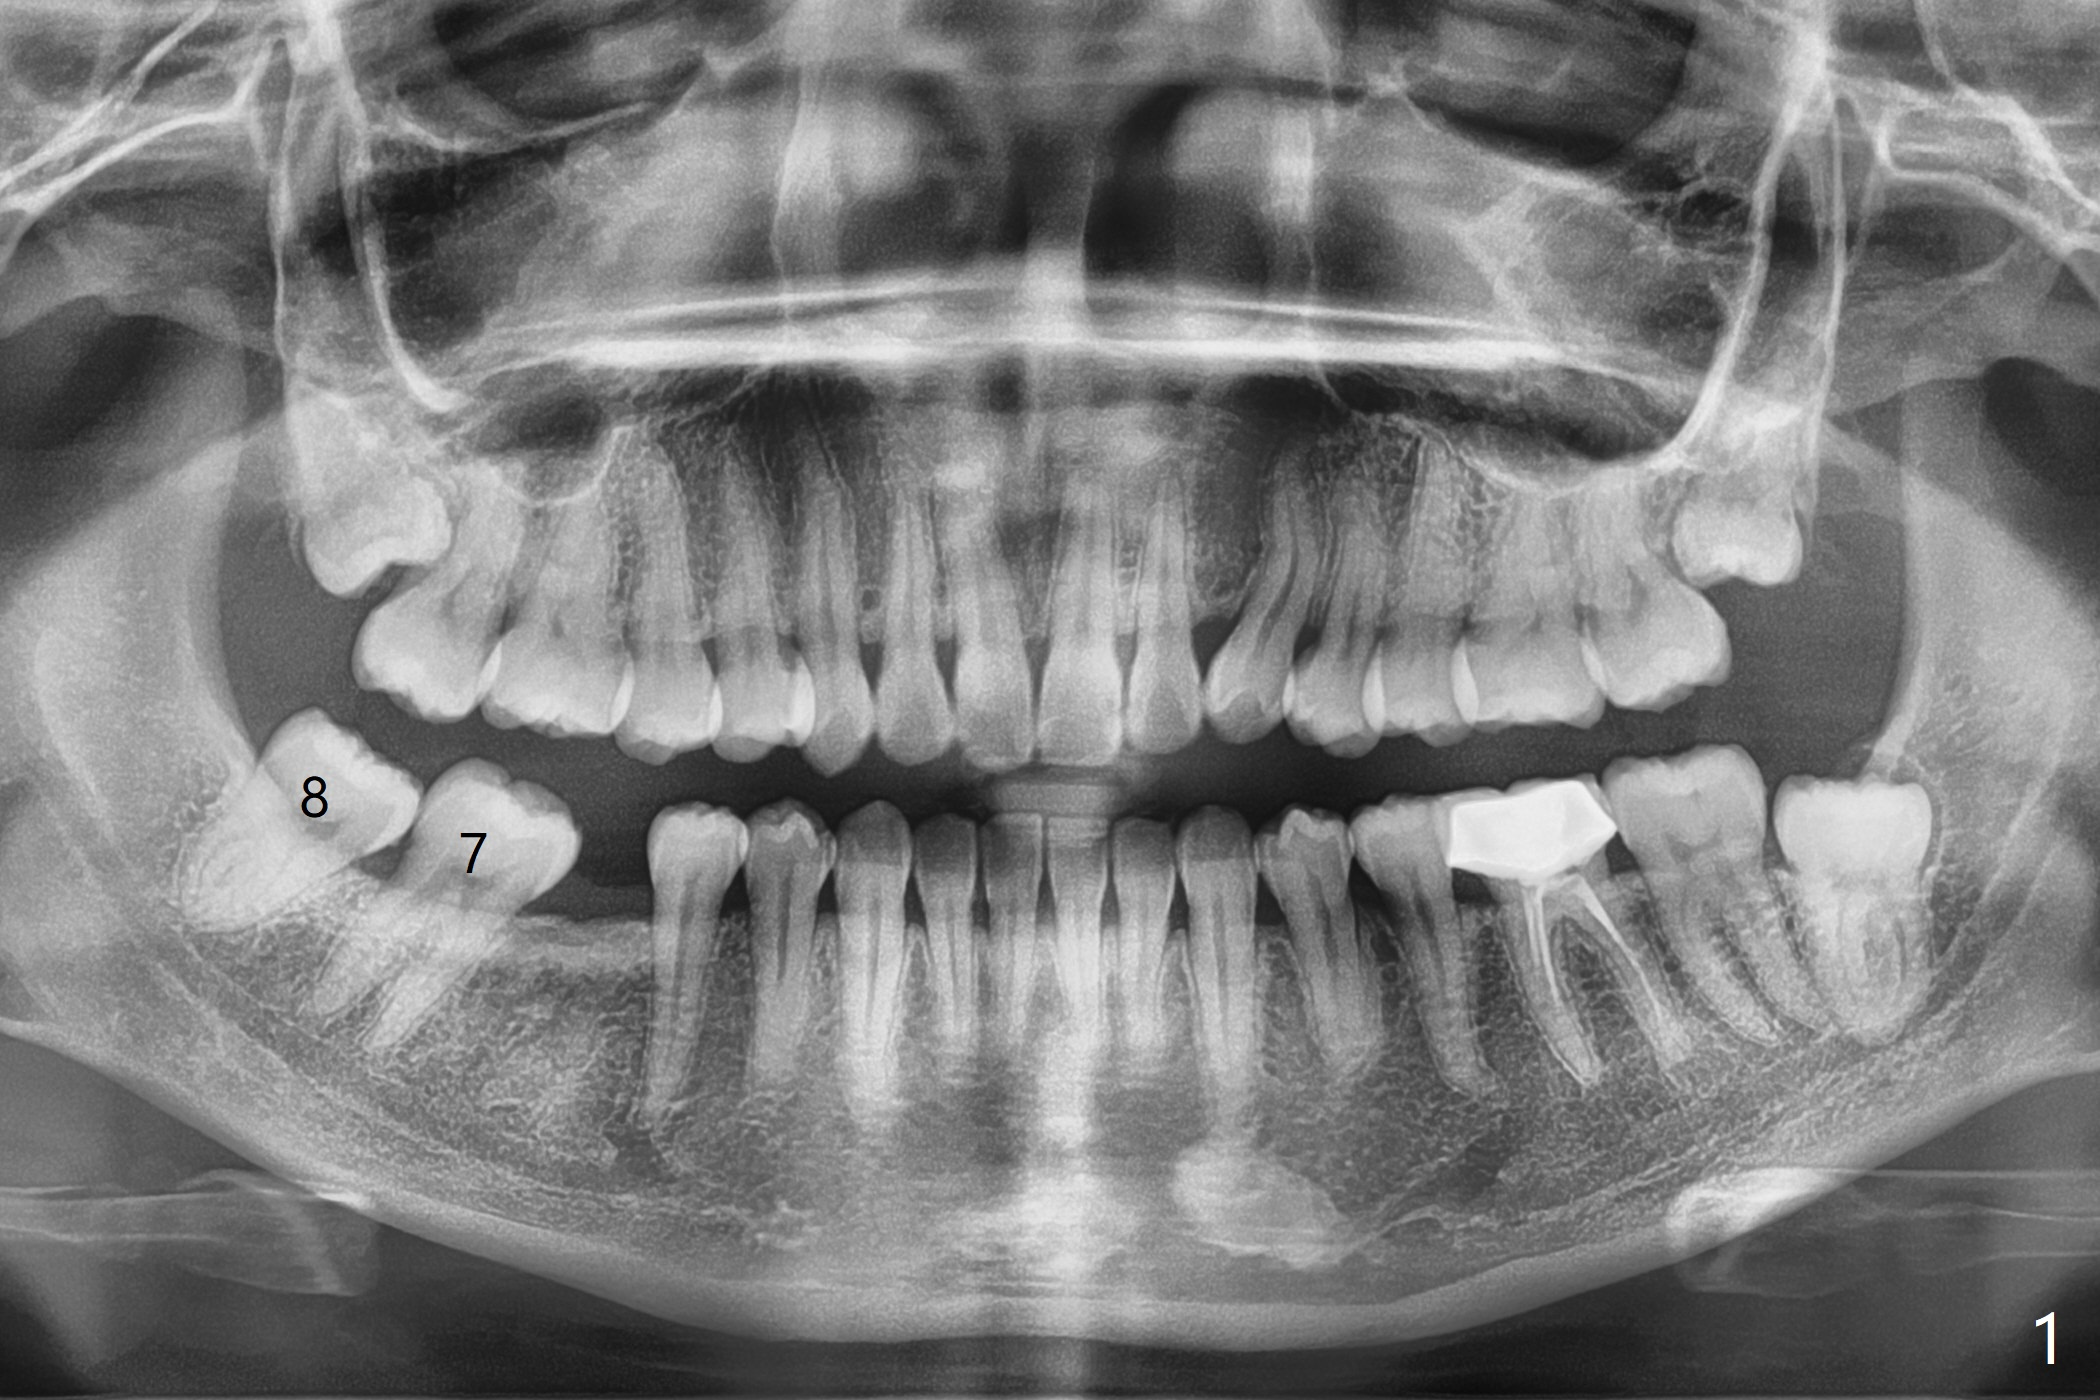

27岁女,小的时候在国内做过牙齿矫正,留下不好印象,不愿意再次矫正。她缺失右下6;7,8明显近中移位(图一,二)。左下7近中颊侧牙尖位于上6,7之间(图三:^),理论上,右下7必须远中移位到8牙位一半(图四)。经过反复讨论(包括前移7,8),病人同意拔除8,做右下后牙区矫正。为了有效7远中移位,拔除8后即刻种植(图五:绿色),植骨(红圆圈),覆盖PRF膜(紫色线)。一旦植牙整合,制作临时牙冠(图六:蓝色;并且提高咬合,这样7有垂直空间后移(直箭头)旋转(弯箭头)),永久性粘固,可能在7,8之间使用power chain,起牵拉作用,棕色方块代表矫正器。一旦6空间扩大,植牙。整合后也可以作为支抗,继续将7远中推移。一定时光,取出智齿植体,完成暂时性支抗作用。